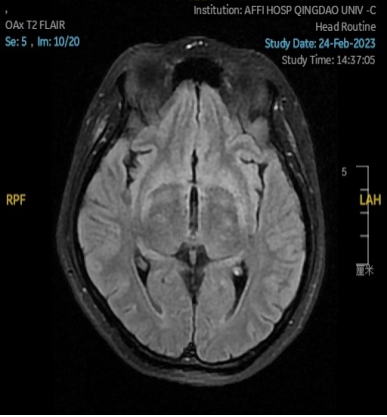

2023.02.24颅脑MR平扫示双侧基底节区及桥脑异常信号,考虑渗透性脱髓鞘综合征,见图3。

图3 2023.02.24颅脑MR成像示双侧基底节区及桥脑见对称性片样长T1长T2信号,FLAIR呈高信号。脑室、脑池、脑沟、脑裂未见明显异常。中线结构居中。

图4 2023.03.27双侧基底节区及桥脑见对称性片样长T1长T2信号,FLAIR呈高信号,较2023-02-24MR所示范围减小。脑室、脑池、脑沟、脑裂未见明显异常,中线结构居中。